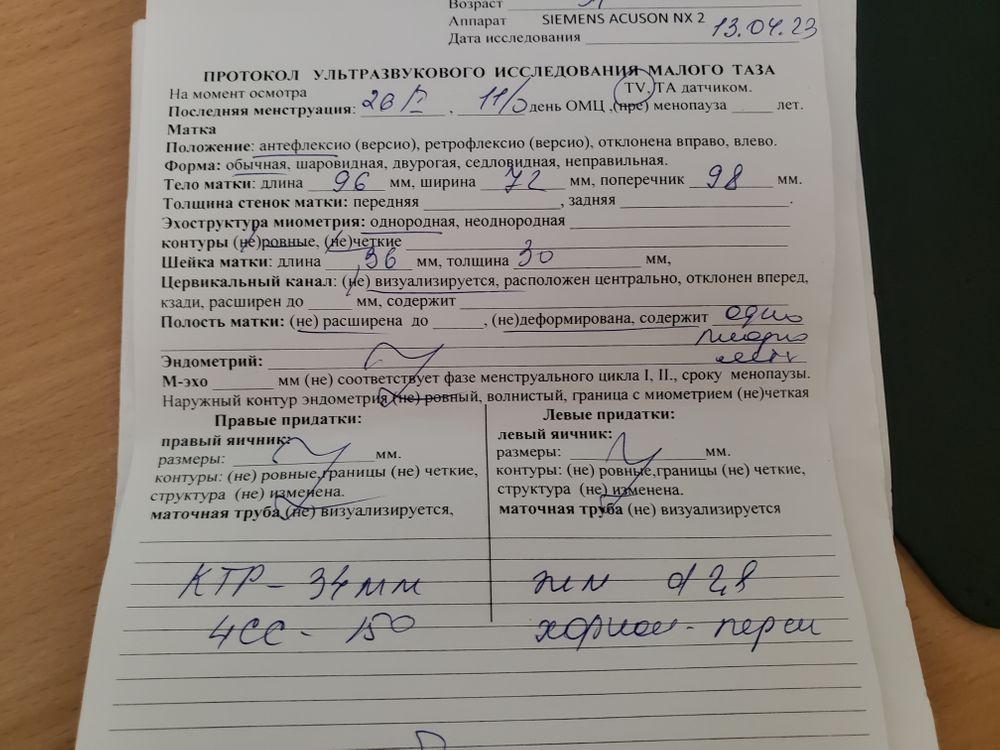

Узи начало 12й недели

УЗИ, КТГ, доплерВ общем недавно встала на учет в ЖК, там мне бабуля гиня дала направления на кучу анализов, врачей и дала мне направление на скрининг 1й, у нее бесплатные были. А я понимаю , что это будет слишком рано, что ей и сказала. Она же сказала- иди, нормально)пришла я сегодня на скрининг, а узистка говорит- че пришла так рано?))) 11 недель ровно сегодня) перенесли на 13-14 недель на начало мая. Сегодня же сделала узи быстро и я сделала фотку малыша)

Все ок в описании? А то отправила меня быстро, толком ничего не сказала